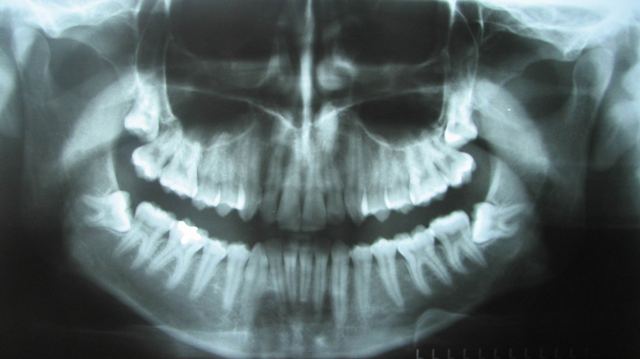

Kirurgi se hitro razvadimo. Ko dobimo v roke nekaj dobrega, starega skorajda ne maramo več. V zadnjih letih smo tako lahko občudovali rentgenske posnetke novih rentgenskih naprav. Ena najbolj osnovnih rentgenskih preiskav v maksilofacialni kirurgiji je ortopantomografski posnetek, ki pokaže zgornjo in spodnjo čeljust z zobmi, delno tudi obnosni votlini v zgornji čeljusti in delno očesni votlini. Pred približno desetimi leti so se pri nekaterih zasebnikih zobozdravnikih pojavile prve naprave za digitalno snemanje ortopanov, ki ponujajo bolj ostro sliko kot klasični ortopani, sevanje, ki so mu pacienti podvrženi, je manjše, sliko pa je mogoče pošiljati v elektronski obliki. Pa vendar nič ne kaže na to, da bi v bližnji prihodnosti v osrednji terciarni ustanovi v Sloveniji zamenjali 20 let star ortopan (slika 1).

Slika 1: Klasični ortopan. Nad zgornjim desnim stranskim sekalcem je videti senco, ki predstavlja nadštevilčen zob.